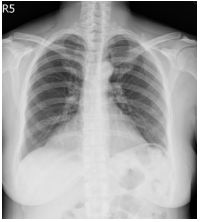

3. This 72-year-old diabetic man was taken to ER for productive cough for 10 days, and rapid progressive dyspnea for 2 days. He also had fever and chill for a week.